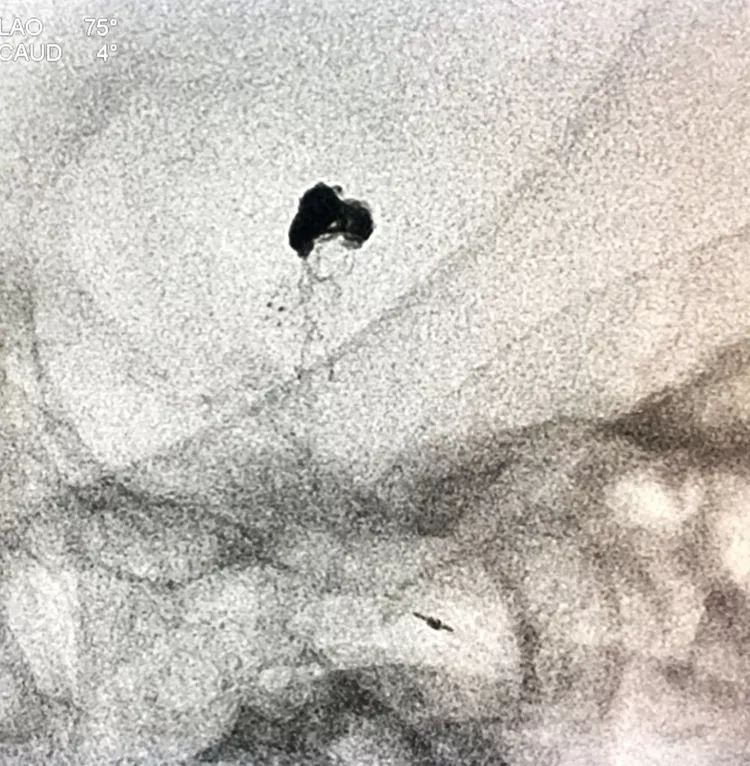

患者女性,80岁,以SAH于2017.5.20急诊入院,CTA示基底动脉顶端动脉瘤。

2.17.5.27 DSA+栓塞

左椎动脉正位造影可以看到指向左方的子瘤。

左椎动脉工作位路图

Sychro14微导丝携Headway21支架导管经左椎动脉-基底动脉进入右侧PCA,因瘤颈主要累及右侧PCA,故计划支架跨基底动脉顶端动脉瘤释放于右侧PCA-基底动脉内。

Echelon10(直头)微导管用Sychro14微导丝引入瘤腔内。

先送入一段弹簧圈

将LVIS支架(3.5×15)跨瘤颈释放于右侧PCA-基底动脉内